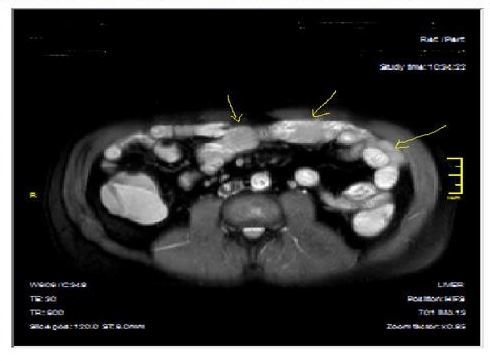

Figure 3a-3b-3c.Diffuse mucosal involvement and extreme luminal narrowing in the terminal ileum due to Crohn’s disease on T2W coronal sequence after OCA administration, stricture and string sign near ileo-ceccal valve in Figure 3b.